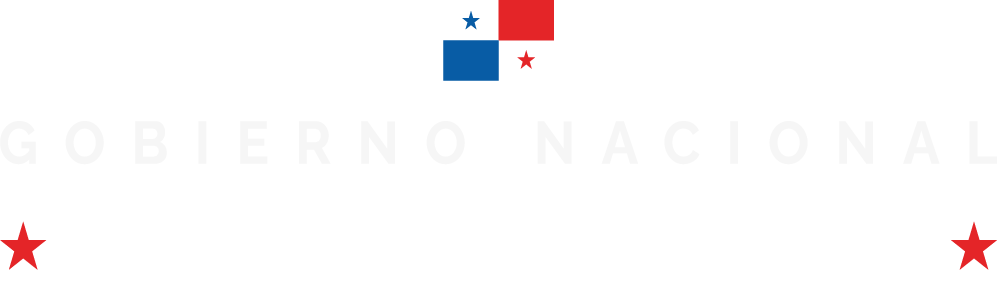

Tabaco y enfermedad pulmonar

El humo del tabaco afecta a los pulmones